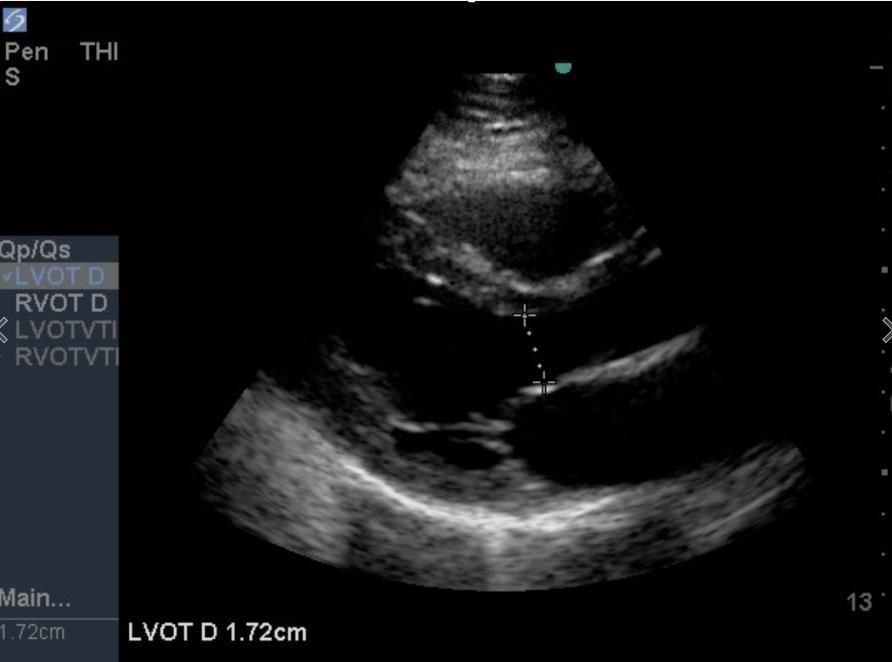

Heart Left Ventricular Outflow Tract (LVOT) Diameter from PLAX Image